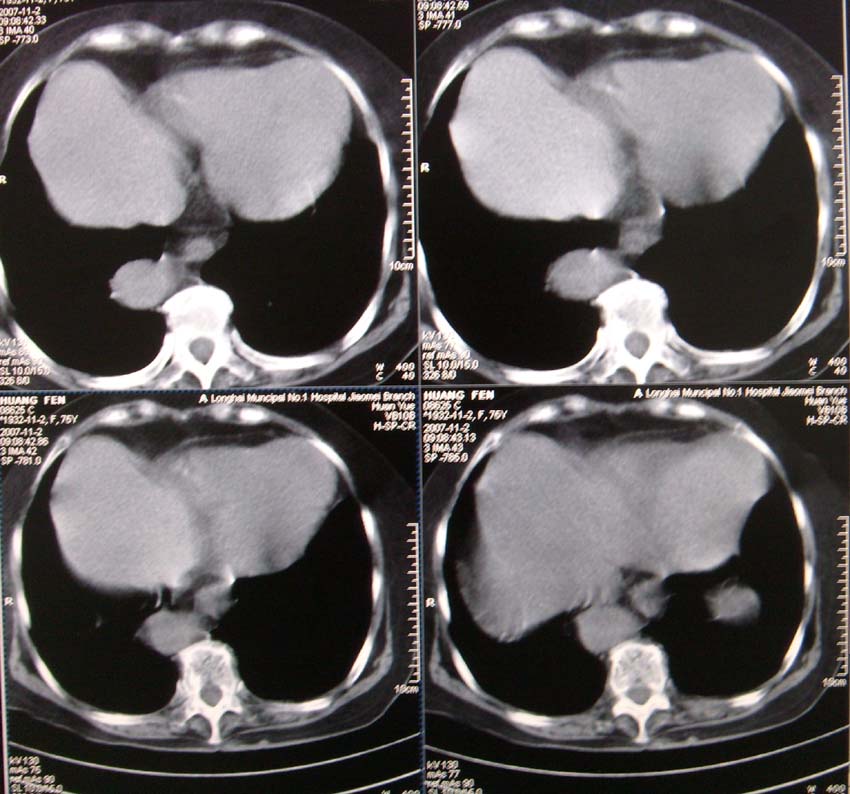

以下是引用nanjing在2007-11-4 12:21:00的发言:[br]降主动脉迂曲移位。